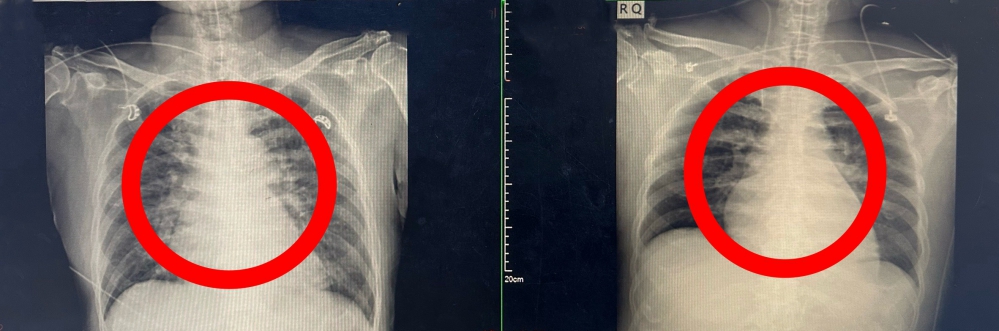

豐原醫院指出,儘管第一時間已給予抗病毒藥物及呼吸與循環支持治療,患者仍出現心因性休克徵象,心肺功能持續惡化,心臟外科隨即決定啟動葉克膜(ECMO)治療,以暫時替代心肺功能,維持全身血液循環與氧氣供應,爭取黃金搶救時間。

同時患者也因休克引發腎衰竭,腎臟科亦即刻介入,啟動連續性靜脈血液過濾術(CVVH),透過24小時持續性血液淨化治療,協助維持體液與電解質平衡、改善代謝性酸中毒狀態,並降低多重器官衰竭風險,為後續器官功能恢復爭取寶貴時間。

在跨科團隊密切合作與整合性重症照護下,患者病況逐步穩定,心肺功能明顯改善,後續順利移除葉克膜及主動脈內氣球幫浦等維生設備,成功脫離加護病房,目前已轉入普通病房持續治療。